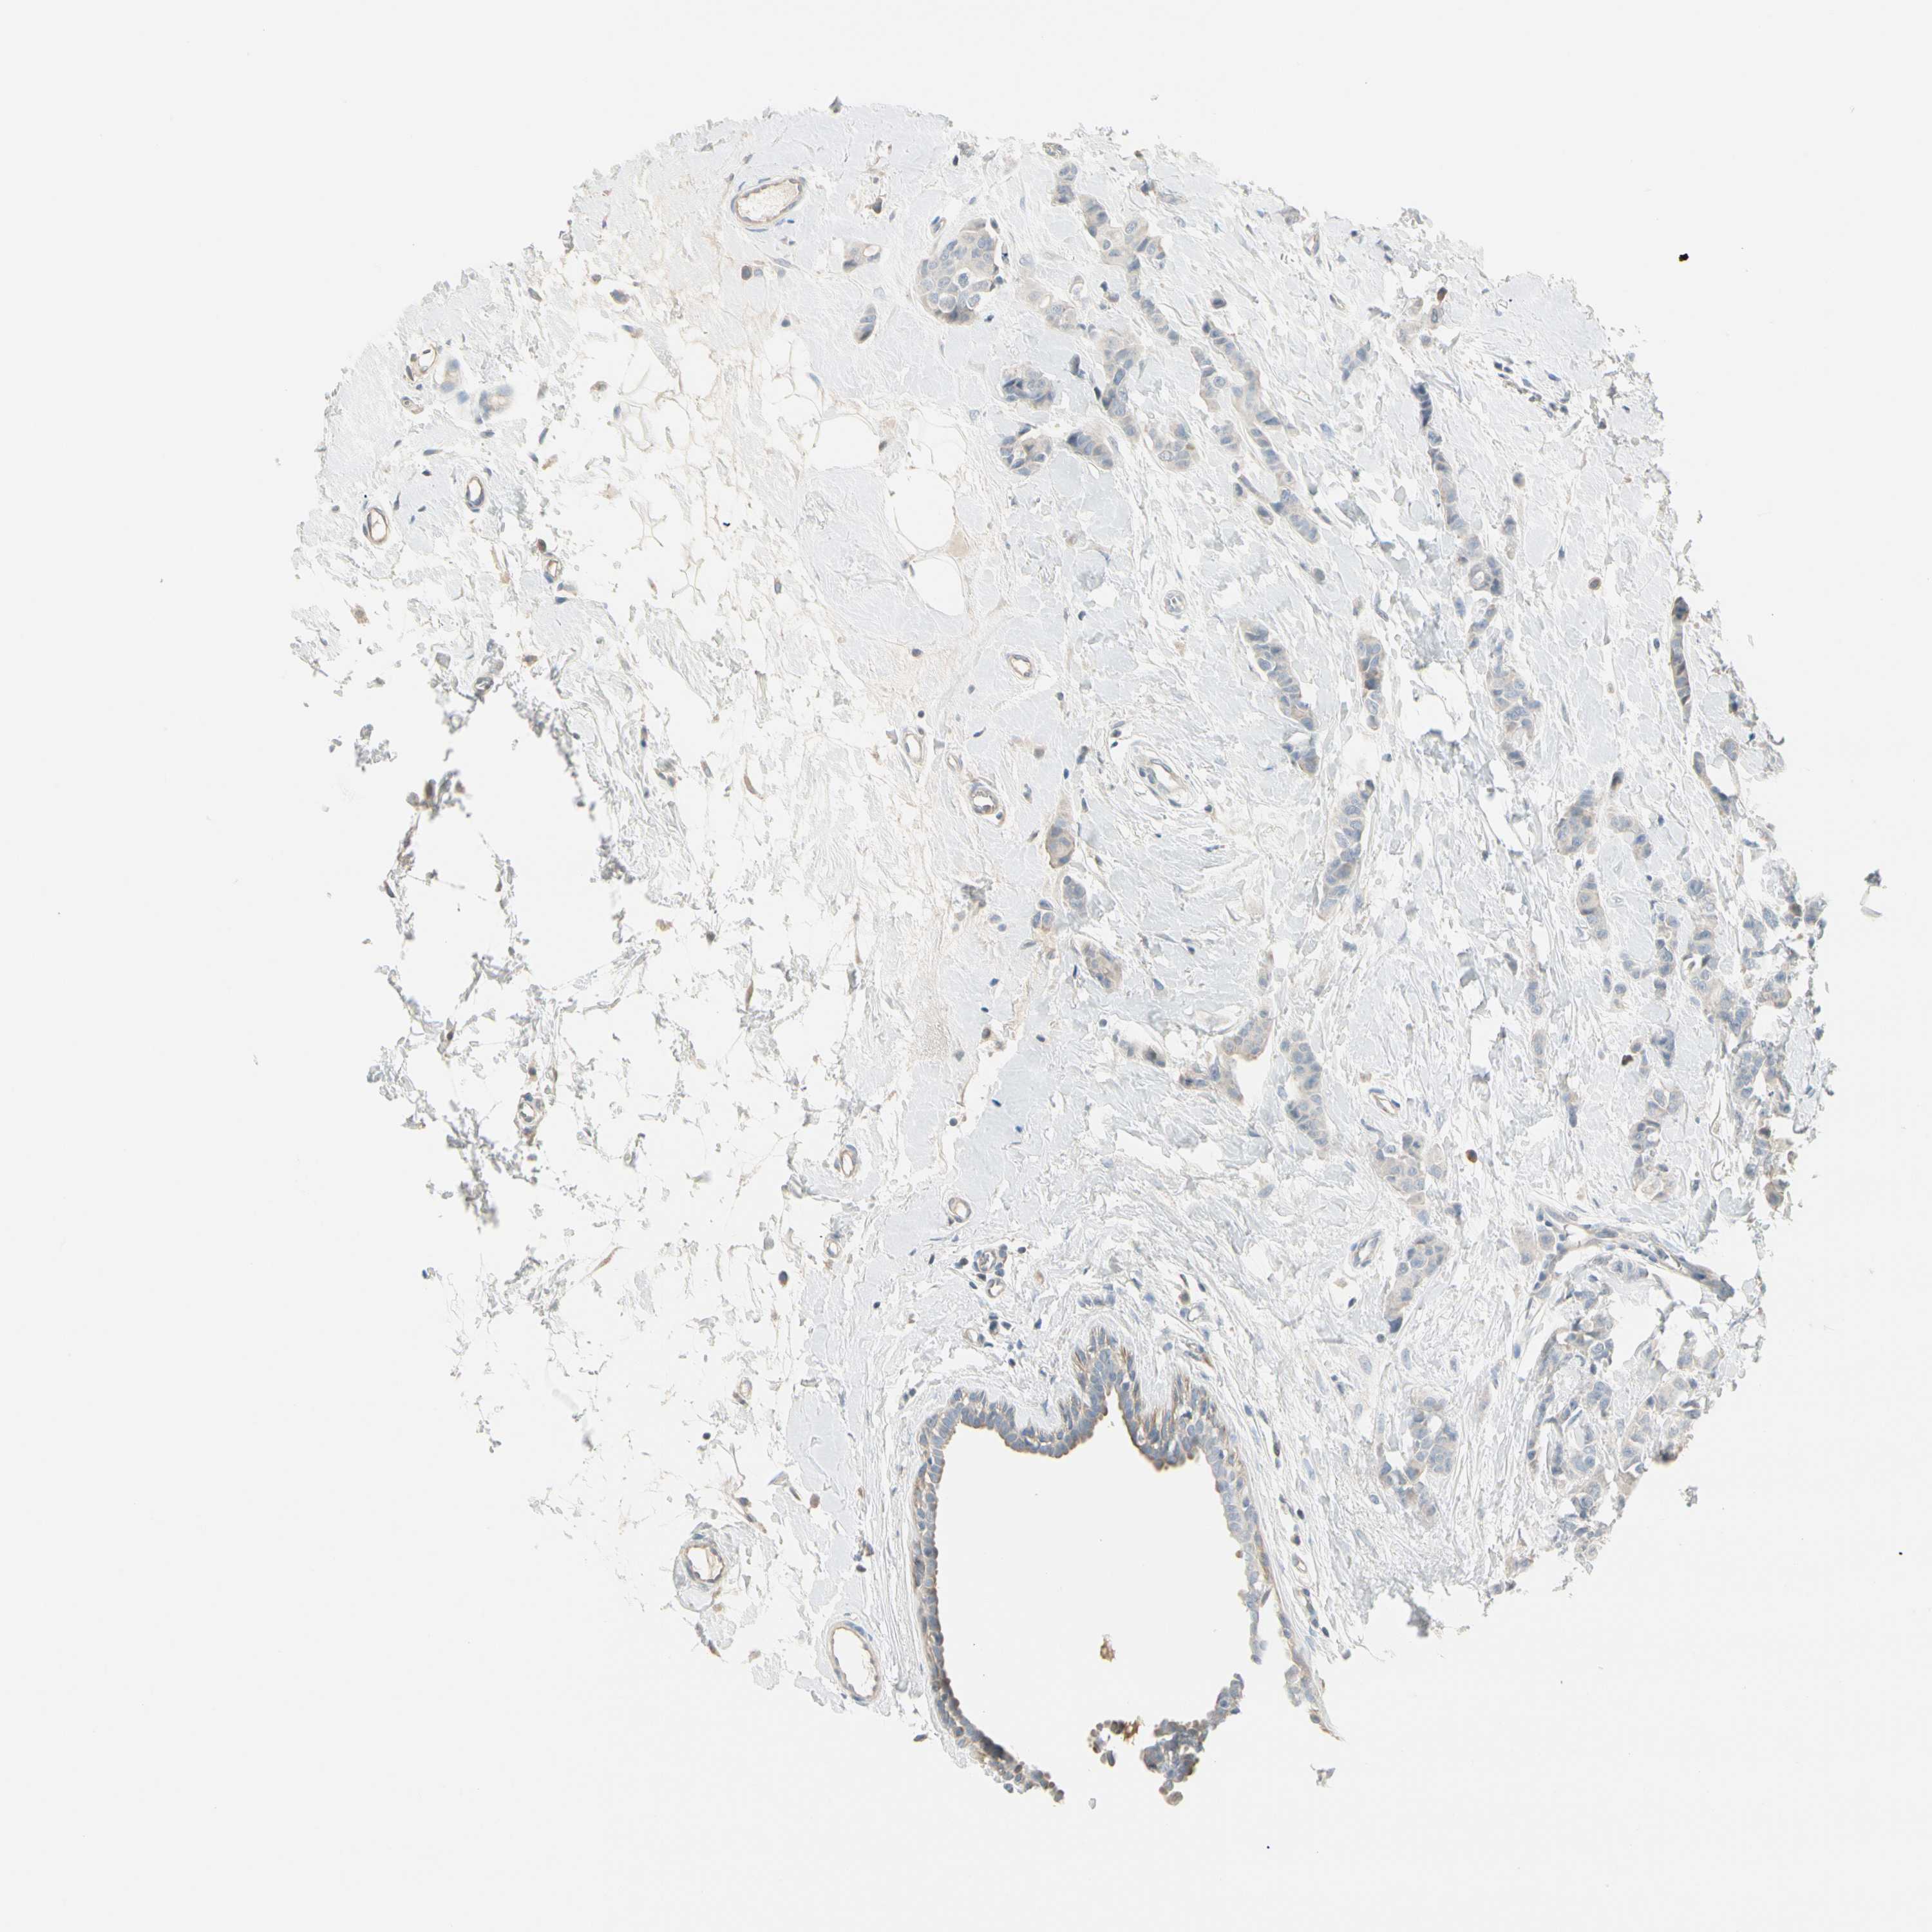

CANCER BREAST CANCER Show tissue menu

BRCA TCGA BRCA VALIDATION PROTEIN EXPRESSION